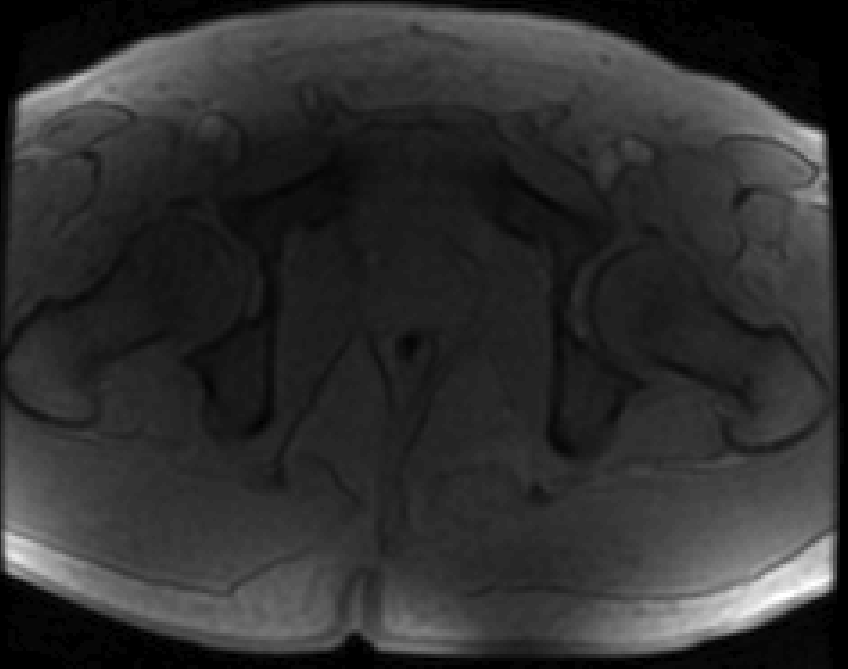

Refer to caption

(a) Magnitude image

(b) PPM map, Phi

(c) Corrected PPM map, 𝚽𝐡subscript𝚽𝐡\bf\Phi_{h}

(d) 𝚽𝐛subscript𝚽𝐛\bf\Phi_{b} field map

Figure 6: Background suppression of a ppm map with water and fat signal. (a): Magnitude of the first echo of a multi echo sequence. (b): PRF map estimation using ARMA technique.(c): Background suppressed PRF map. (d): Estimated background field map in ppm. The fat and water peak is aliased with 4.324.324.32 ppm due to the chosen echo spacing. the fat-water boundary. The labels 1 and 2 are water and fat ROIs that are used to determine the CNR gain of the method.

An MFGRE sequence was used to collect using a 3T scanner (SIGNA; GE Healthcare Technologies, Waukesha, WI) 16 echoes with echo spacing of 1.816ms1.816𝑚𝑠1.816ms, TR=75ms𝑇𝑅75𝑚𝑠TR=75ms, Matrix 128×128128128128\times 128 and Pixel Bandwidth of 651.016Hz651.016𝐻𝑧651.016Hz. Figure 6 (a) illustrates the magnitude of the first echo of a slice through the pelvis. The multi echo data is processed pixel wise by the ARMA technique. The resulting PRF in ppm at each pixel is illustrated in Panel (b). The dark areas in panel (b) are subcutaneous lipid. Inhomogeneities of the PRF can be seen near the air inclusion in the middle and throughout the image, in particular in the lipid regions. The result of the background suppression technique is shown in Panel (c), which illustrates, that most of the background inhomogeneities have been removed. Note the fat-water ppm difference is about 1.16ppm1.16𝑝𝑝𝑚1.16ppm and not the expected shift of about 33.5ppm33.5𝑝𝑝𝑚3-3.5ppm. This is a consequence of aliasing introduced by the finite sampling in echo direction. If the aliasing is taken into account by adding the bandwidth of 4.3212ppm4.3212𝑝𝑝𝑚4.3212ppm, then the fat-water shift is 3ppm3𝑝𝑝𝑚3ppm as expected. The pixel wise difference of the images in Panels (b) and (c) is shown in Panel (d). Note that the estimated background field 𝚽𝐛subscript𝚽𝐛{\bf\Phi_{b}} is smooth in areas of transitions of fat and water. The map is not necessarily smooth in areas of low signal, however a correct estimation of the background in low signal areas is not a well-posed problem.